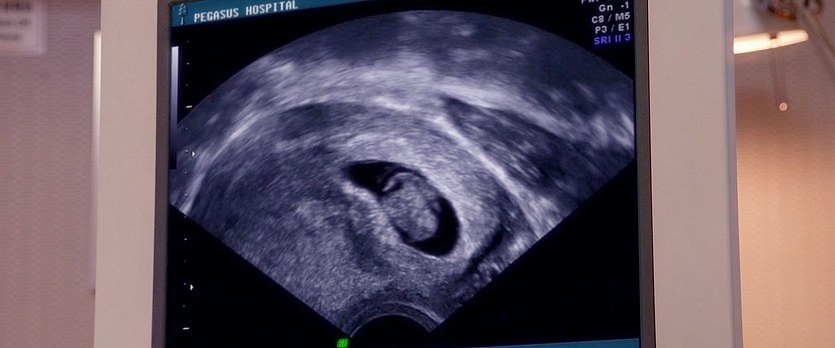

圖片名稱:Hello.Babies.2014_05714

圖源尺寸:Blu-ray 1080p